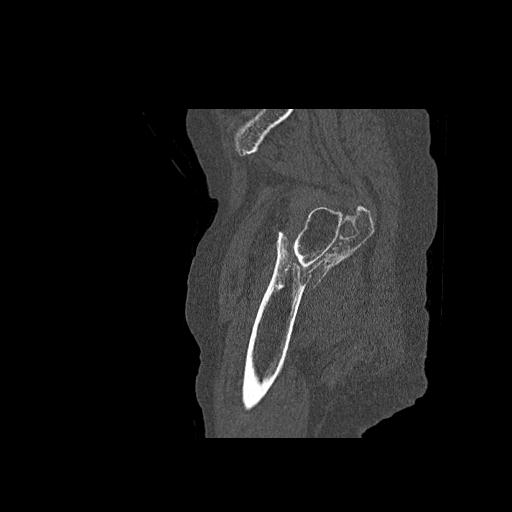

49554 3/13 膝 4R 3/16 4R 1/18 2R 78歳男性 膝蓋骨骨折